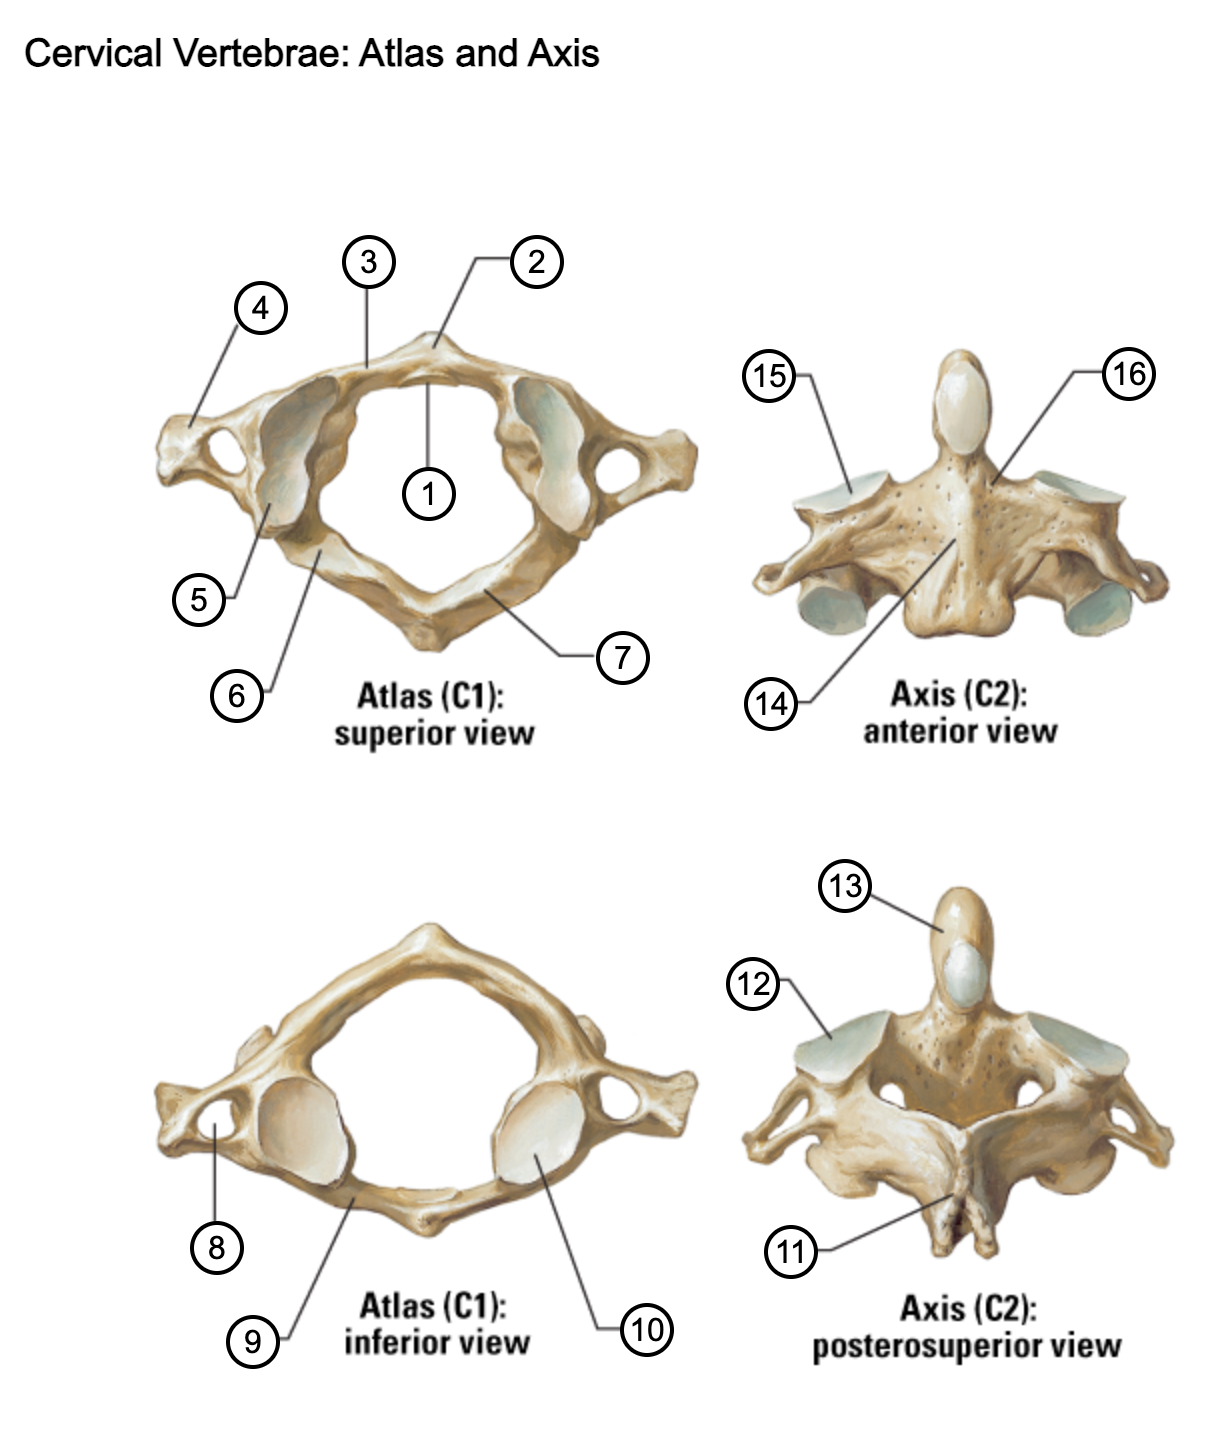

1

facet for dens

2

anterior tubercle

3

anterior arch

4

transverse process

5

superior articular surface of atlas

6

groove for vertebral artery

7

posterior arch

8

transverse foramen

9

anterior arch

10

inferior articular surface of atlas

11

spinous process

12

superior articular facet

13

dens of axis

14

body of axis

15

superior articular facet for atlas

16

pedicle of vertebral arch